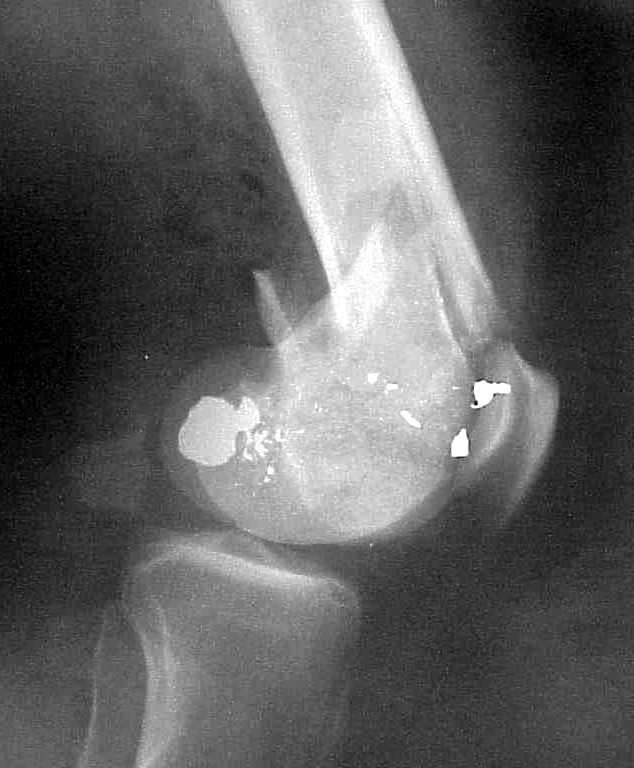

place one anterior to where IMN will go if anterior cortex if insufficient and AP screws on either side of the IMN out of the trochlea to provide some additional varus/valgus stability. I worry about the leg going into valgus w/the lack of lateral cortex.

See attached case that was done several years ago before LISS. He had comminuted trochlea and anterior blocking screws were used to prevent anterior IMN cut-out.